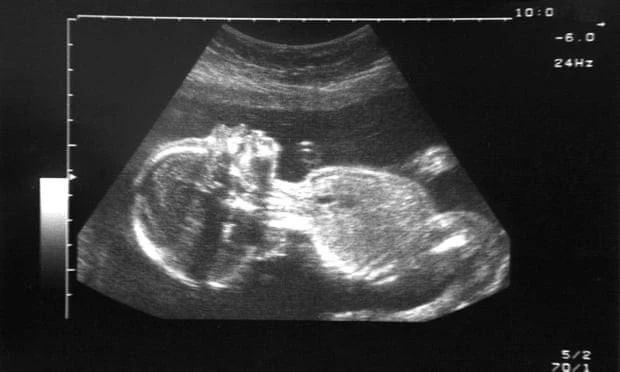

空气中的黑碳颗粒可以出现在胎盘中是怎么回事,是真的吗?2019年09月18日是本文发布时间是这个时间。下面一起来看看到底怎么回事吧。

空气中的黑碳颗粒可以出现在胎盘中

研究发现,暴露在高水平黑碳颗粒环境中的女性,胎盘中的黑碳颗粒也更多。

空气中的黑碳颗粒主要来自化石燃料的燃烧,此前的研究已经证明,这类颗粒对妊娠有害,例如,它们与早产或低出生体重相关。在一项发表于《自然·通讯》的最新研究中,研究人员利用高分辨率成像技术,从5例早产和23例足月生产的胎盘靠胎儿一侧检测到了黑碳颗粒。其中,暴露在高水平黑碳颗粒环境中的女性,胎盘中的黑碳颗粒也更多。研究人员也表示,还需要开展进一步的研究来明确这些颗粒是否能够抵达胎儿。 |